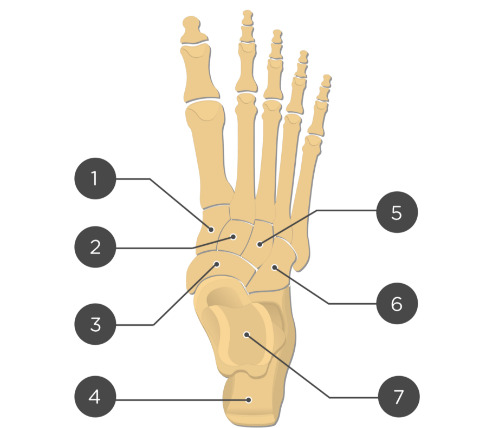

Two unlabeled illustrated images, figures 1 and 2, of the foot and one unlabeled x-ray image, figure 3, were selected. Each image was inputted into ChatGPT Version 4o and the model was prompted to identify the bones depicted in each image using the following prompt.

Prompt 2: ‘Identify the structures labeled in this image’

Out of 11 labels, 3 were identified correctly, resulting in an accuracy of 27%.

Prompt 2: Identify the structures labeled in this image